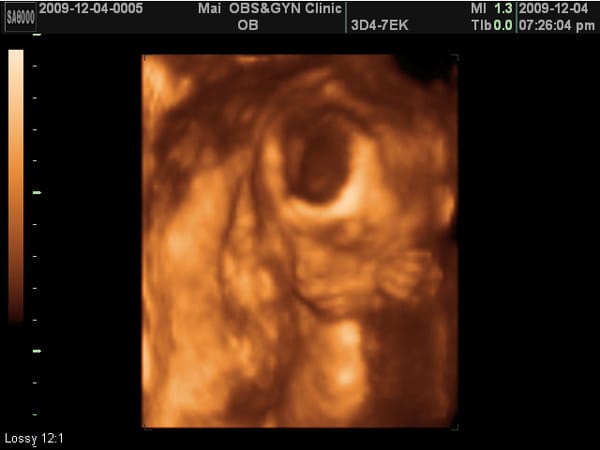

小老虎第四次產檢,驗尿ok,血壓ok,母親體重60.5KG。 小老虎上次產檢3百多公克,這次5百多公克,換句話說,這四周胖了2.7KG,結結實實胖在母體。 非常奇特,因為這幾周來我定時吃三餐沒吃消夜,這樣反而胖? 超音波照片拿到手之後,傅看著她的鼻子,說:鼻子好像比較挺喔。 小老虎還是趴著的。 有點擔心她一直趴會不會怎樣? 這次的產檢因為看不到小老虎的臉,所以醫生就用4D的給我們看 […]…